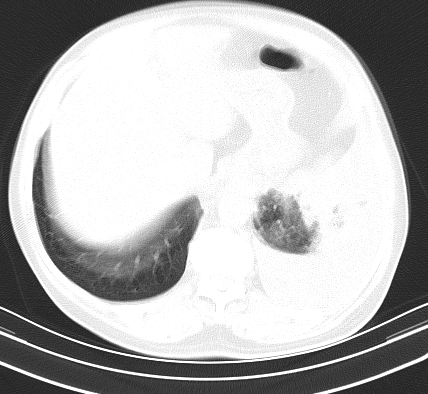

以下是引用老爱克斯新网客在2008-7-31 6:30:00的发言:[br]左肺上叶大片状病灶,左肺上叶支气管狭窄呈鼠尾状,左肺门增大,纵隔内见肿大淋巴结,左侧胸腔积液,余肺清晰。左肺中心型肺癌淋巴结转移,

以下是引用zjb在2008-7-31 6:32:00的发言:[br]左侧中心性肺癌 阻塞性肺炎 肺不张 胸腔积液 建议气管镜

以下是引用zjzjr在2008-7-31 8:45:00的发言:[br]考虑左侧中心性肺癌伴阻塞性肺炎,左肺上叶肺不张,纵隔淋巴结转移;左侧胸腔积液。建议行纤支镜检查。

以下是引用sdzyy在2008-7-31 8:47:00的发言:[br]病灶较治疗前有所进展,胸水增多, 左侧中心性肺癌 并 阻塞性肺炎 肺不张 胸腔积液 可能性大; 建议气管镜检查。 [br] [br]